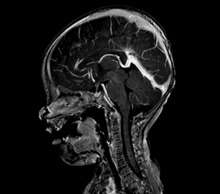

| Large arteriovenous malformation of the parietal lobe | |